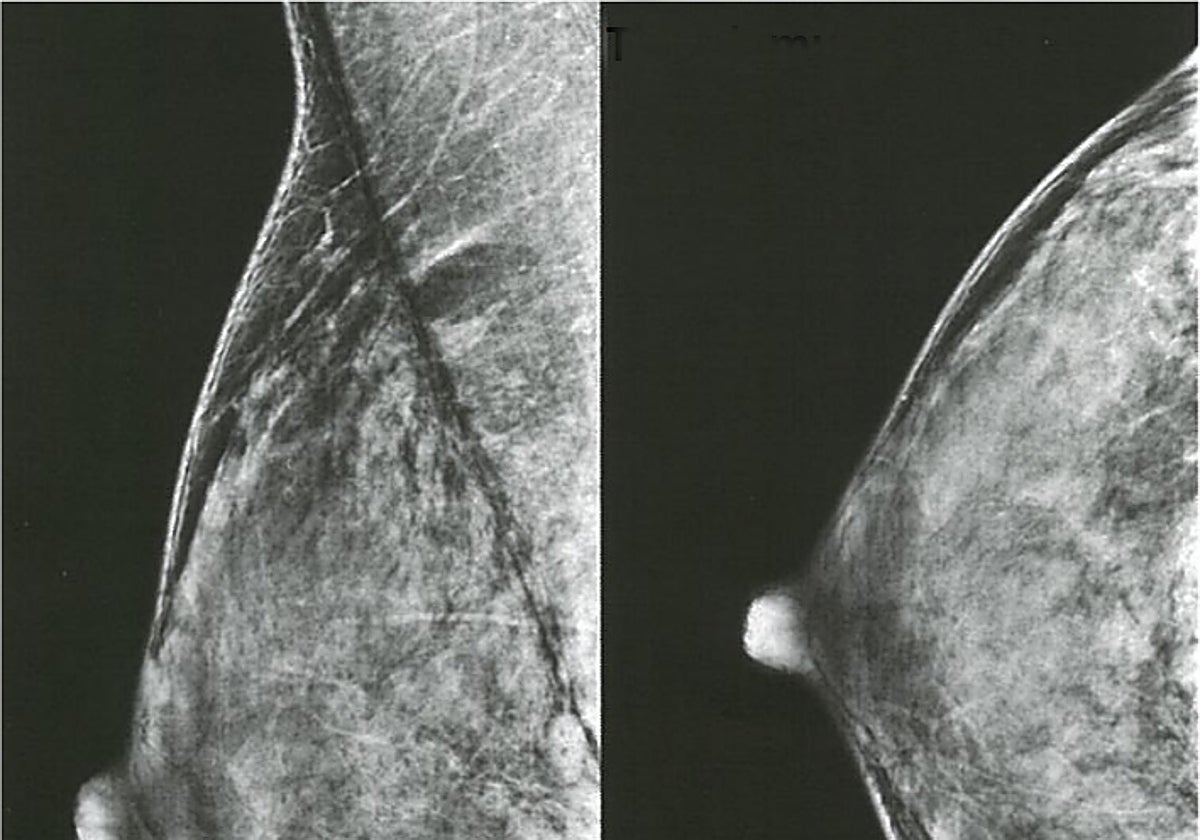

Las pruebas que detectan el cáncer de mama antes de que se palpe

Iniciar sesiónEl primer ensayo clínico aleatorizado con más de 80.000 mujeres ha demostrado que la Inteligencia Artificial (IA) es capaz de ver más que el ojo humano. O incluso más que un par de ellos. El propósito de la investigación era conocer la eficacia ... y seguridad de esta tecnología a la hora de buscar lesiones sospechosas de cáncer de mama en una mamografía para saber si se puede convertir en el mejor asistente del radiólogo. Y la respuesta ha sido afirmativa.

El estudio, publicado en The Lancet Oncology, muestra en un análisis preliminar que contar con la ayuda de la IA es tan útil como poner a dos radiólogos especializados en mama a revisar al mismo tiempo las mamografías en busca de tumores. Detectaron un 20% más de tumores que utilizando la metodología tradicional con la doble revisión de dos especialistas. Además de reducir casi a la mitad la carga de trabajo de los médicos lo hicieron sin aumentar los falsos positivos.

Este nuevo trabajo se realizó con las mamografías de 80.033 mujeres suecas de entre 40 y 80 años. La metodología fue la siguiente: la inteligencia artificial analizó la imagen de la mamografía y predijo el riesgo de cáncer en una escala del 1 al 10, donde uno representa el riesgo más bajo y 10 el más alto. Si la puntuación de riesgo era inferior a 10, un radiólogo analizaba más la imagen, mientras que si el sistema de IA predecía una puntuación de riesgo de 10, dos radiólogos estudiaban la placa.